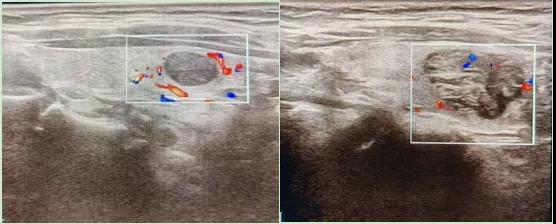

二、彩超如何“揪出”甲狀腺瘤?

彩超是一種無(wú)創(chuàng)、無(wú)輻射的檢查手段,被譽(yù)為甲狀腺的“高清攝像頭”。它的原理是:

超聲波探測(cè):通過發(fā)射高頻聲波,生成甲狀腺的實(shí)時(shí)圖像。

彩色血流顯示:用紅藍(lán)色標(biāo)記血流信號(hào),區(qū)分腫瘤的供血情況。

醫(yī)生會(huì)通過以下特征判斷腫瘤性質(zhì):

1.形態(tài):良性多呈圓形,邊界清晰;惡性可能不規(guī)則、邊緣模糊。

2.回聲:低回聲結(jié)節(jié)風(fēng)險(xiǎn)較高(像“烏云”一樣暗)。

3.鈣化:細(xì)小砂礫樣鈣化提示惡性可能。

4.血流信號(hào):惡性結(jié)節(jié)常有豐富紊亂的血流。